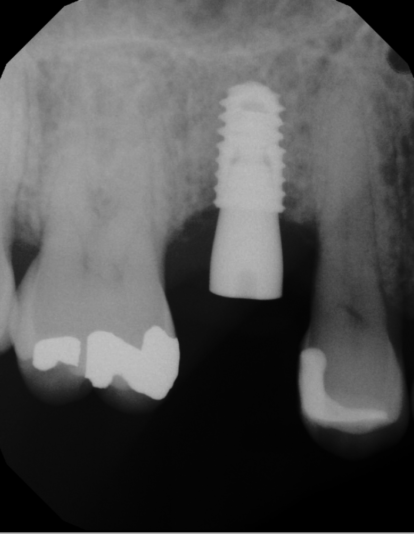

2nd/3rd picture – Week 3 post op

At the post op visit, noticed some purulence around the healing abutment along with the buccal tissue being flappy without any kind of closure. Also took a PA and noticed a distinct RL around the implant. Shit sucked.

The implant you can back out easily with the hand torque wrench at this point. If you want to replace it, it look like you have space for a longer implant. Remove the implant, currette and take the osteotomy deeper and place another implant, bury it this time. No need to wait and relay the case.

Any chance you overheated the bone during osteotomy prep? You could put patient on CHX and wait to take an xray at 1 month post placement to check on the bone, all may not be lost yet. If it looks worse, you can still remove and replace immediate or graft and delayed.